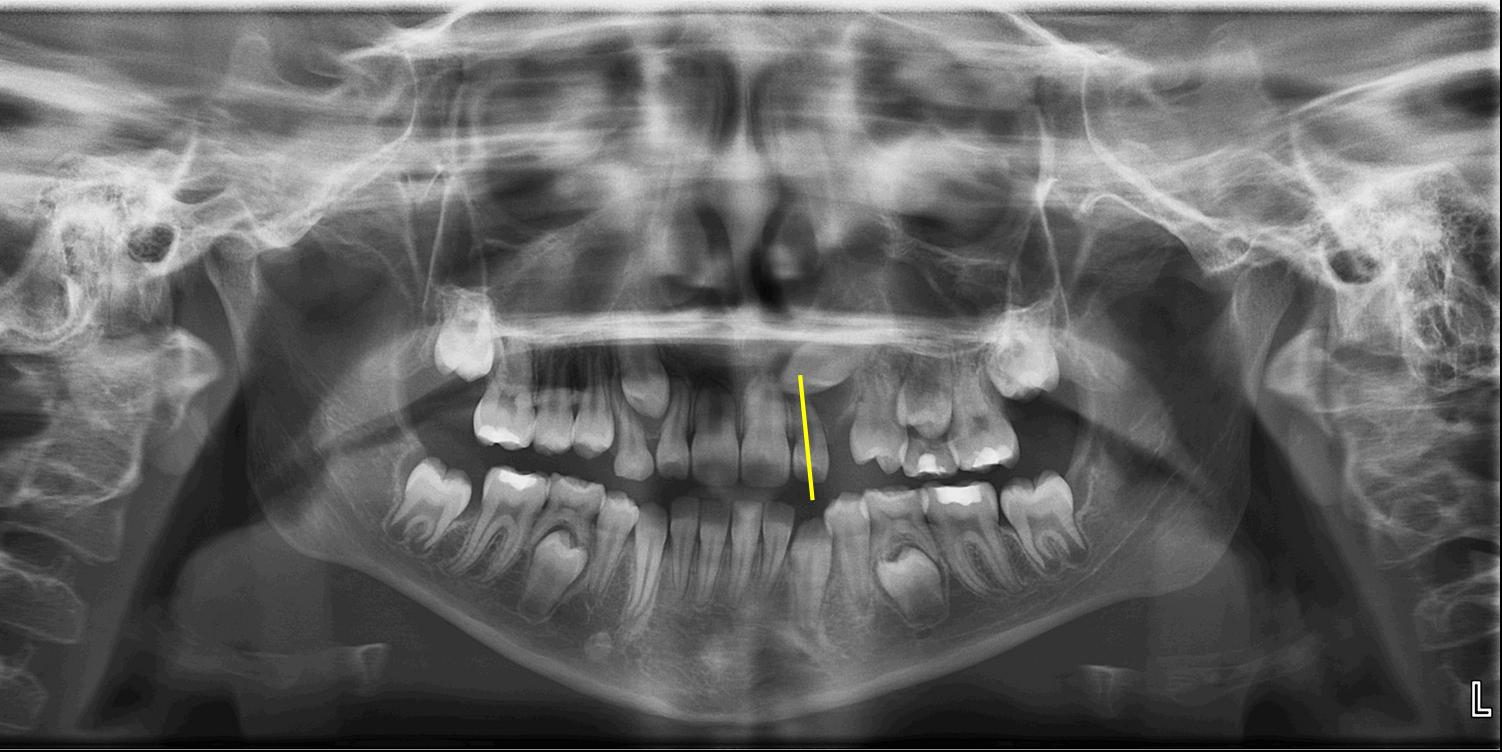

Evaluate the positions of the unerupted canines on a panoramic radiograph for all patients at ages eight and nine. Whenever the crown of the canine crosses the long axis of the lateral incisor, as shown in Figure 1, the canine may become impacted.

Look at the size of the follicle around the unerupted canine. Canines that are having problems with eruption tend to have larger than normal follicles, as seen in Figure 2.

Patients with ectopically erupting maxillary canines are at risk for root resorption on the adjacent lateral incisors. It is a misconception that lateral incisor root resorption is the result of orthodontic treatment. Lateral incisor root resorption resulting from orthodontic forces is controllable and is usually minimal. Patients presenting with root resorption at the start of orthodontic treatment will experience the most root resorption. This is due to the poor position of the canine and resorption of the lateral incisor root by the canine, not by orthodontic forces. It is unusual to see root resorption as severe as that of the nine-year-old patient show in Figure 5; however, such severe root resorption may be avoided by recognizing a potential problem early.